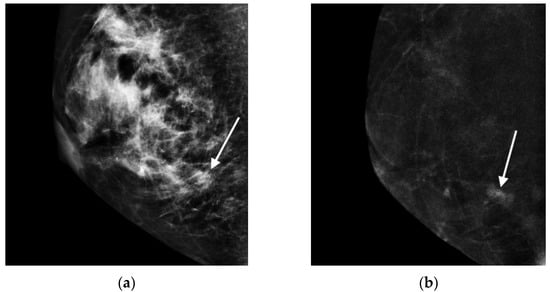

Contrast-Enhanced Mammographic Features of In Situ and Invasive Ductal Carcinoma Manifesting Microcalcifications Only: Help to Predict Underestimation?

- Cheung, Y.C.; Juan, Y.H.; Lin, Y.C.; Lo, Y.F.; Tsai, H.P.; Ueng, S.H.; Chen, S.C. Dual-Energy Contrast-Enhanced Spectral Mammography: Enhancement Analysis on BI-RADS 4 Non-Mass Microcalcifications in Screened Women. PLoS ONE 2016, 11, e0162740. [Google Scholar]